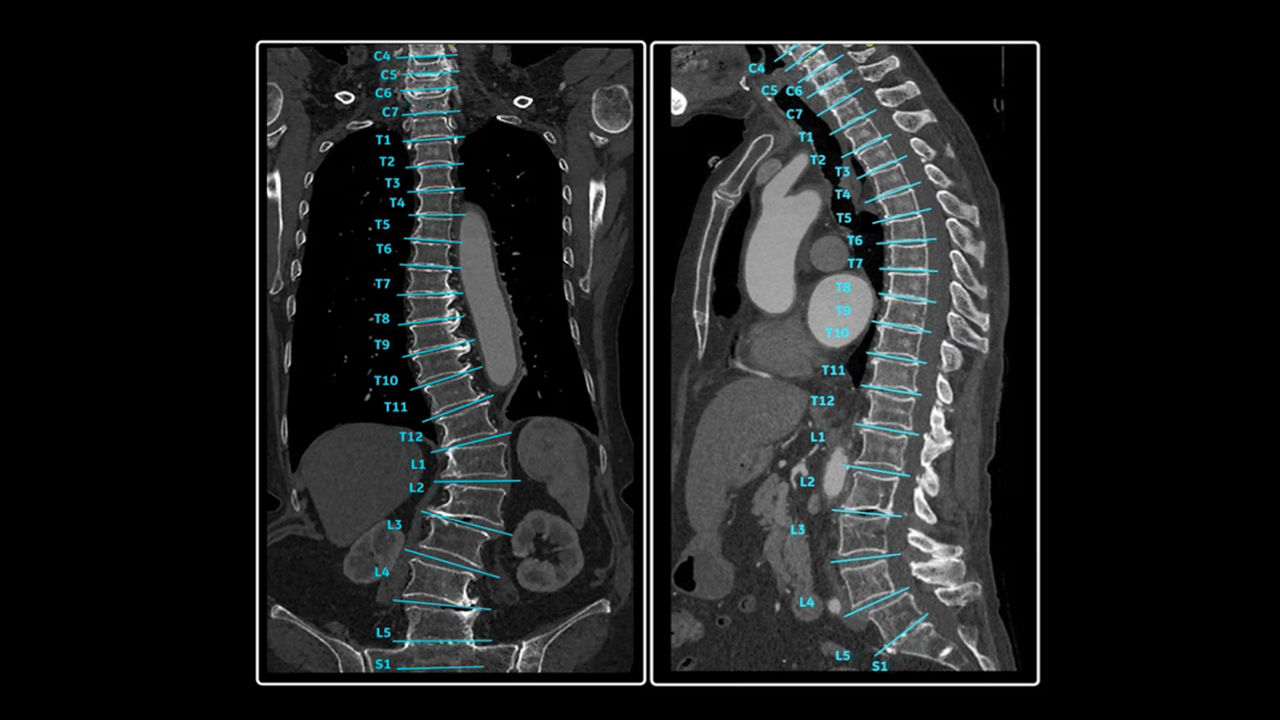

<p>Spine Auto Views</p>

Learn more

<p>Head Auto Views</p>

<p>Bone VCAR</p>

<p>VesselIQ Xpress with AutoBone Xpress</p>